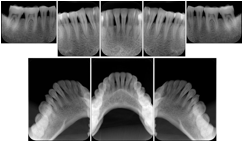

OO.1.2 Ophthalmology

1. A patient in rural Canada visits a general ophthalmologist and is found to have diabetic macular edema. The general ophthalmologist would like to discuss the case with a retina specialist before performing laser surgery. A fluorescein angiogram is done with multiple retinal images taken in a timed series after an intravenous injection. The images along with a Structured Display are shared via a Health Information Exchange with a retina specialist in Calgary, who opens them using his Ophthalmology EMR software and consults via phone with the general ophthalmologist. Both physicians view the images in the same layout so the retina specialist can provide accurate guidance for treating the patient.

2. A patient in rural Iowa visits his primary care physician for management of diabetes. Three non-mydriatic (patient's eyes are not dilated) photographs are taken of the back of each eye, and forwarded electronically along with a Structured Display to an ophthalmologist in Iowa City. The ophthalmologist reads the photos in an agreed upon layout so there is no mistake about what portion of which eye is being viewed. The ophthalmologist is able to tell the primary care physician that his patient does not need to come to Iowa City for face to face ophthalmologic care, but that there is a particular view of the left eye that should be photographed again in 6 months.

Ophthalmic Retinal Study Structured Display

Figure OO-3. Ophthalmic Retinal Study Structured Display